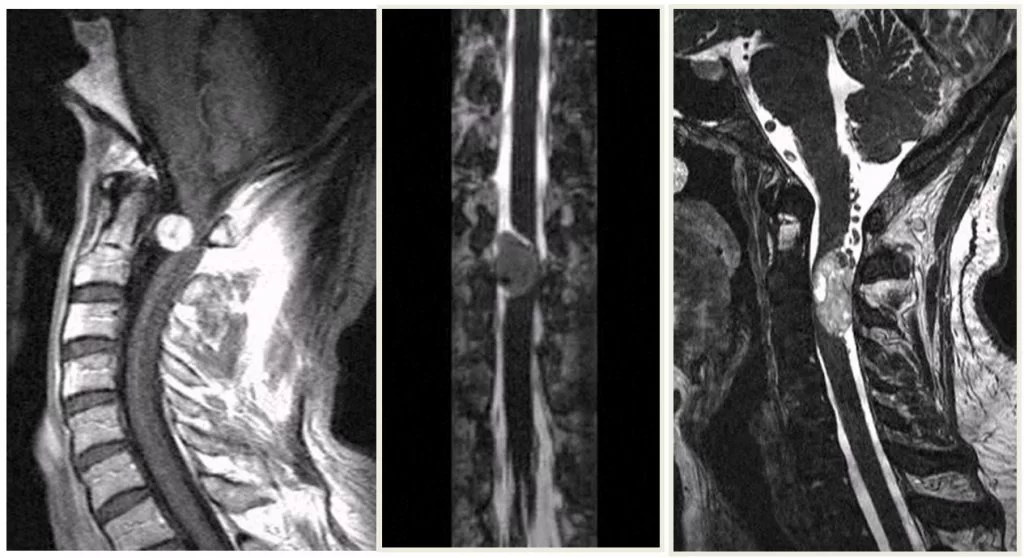

Οι ενδομυελικοί όγκοι αναπτύσσονται εντός του νωτιαίου μυελού (Εικόνα 1). Η συχνότητά τους σε σχέση με τους υπόλοιπους όγκους νωτιαίου μυελού είναι 5%. Τα αστροκυττώματα (στα παιδιά κυρίως) και τα επενδυμώματα (στους ενήλικες κυρίως) είναι οι συχνότεροι τύποι. Λιγότερο συχνοί τύποι είναι τα αιμαγγειοβλαστώματα, σηραγγώδη αγγειώματα και τα λιπώματα.

Οι ενδοσκληρίδιοι-εξωμυελικοί εντοπίζονται εντός της σκληράς μήνιγγας (δηλαδή του περιβλήματος του νωτιαίου μυελού) αλλά εκτός του νωτιαίου μυελού (Εικόνα 2). Η συχνότητα είναι περίπου 40% των όγκων σπονδυλικής στήλης. Οι πιο συχνοί τύποι είναι τα μηνιγγιώματα, τα επενδυμώματα του τελικού νηματίου, τα σβαννώματα και τα νευρινώματα. Πρόκειται στην πλειοψηφία τους για καλοήθεις όγκους.